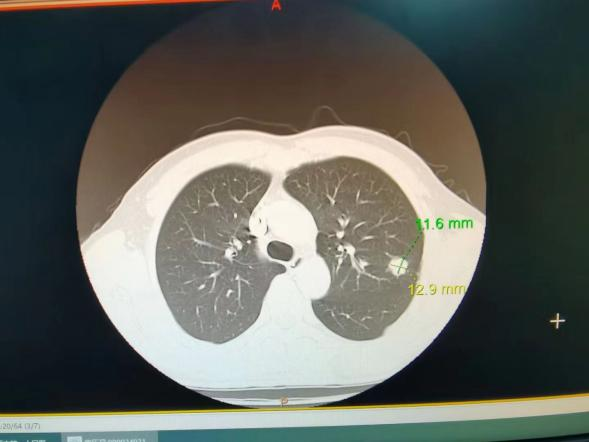

肺癌晚期ct报告单

肺癌晚期ct报告单,

肺结节等于肺癌吗3mm肺结节消失案例

肺部ct报告单模板电子版

肺癌ct早期报告单